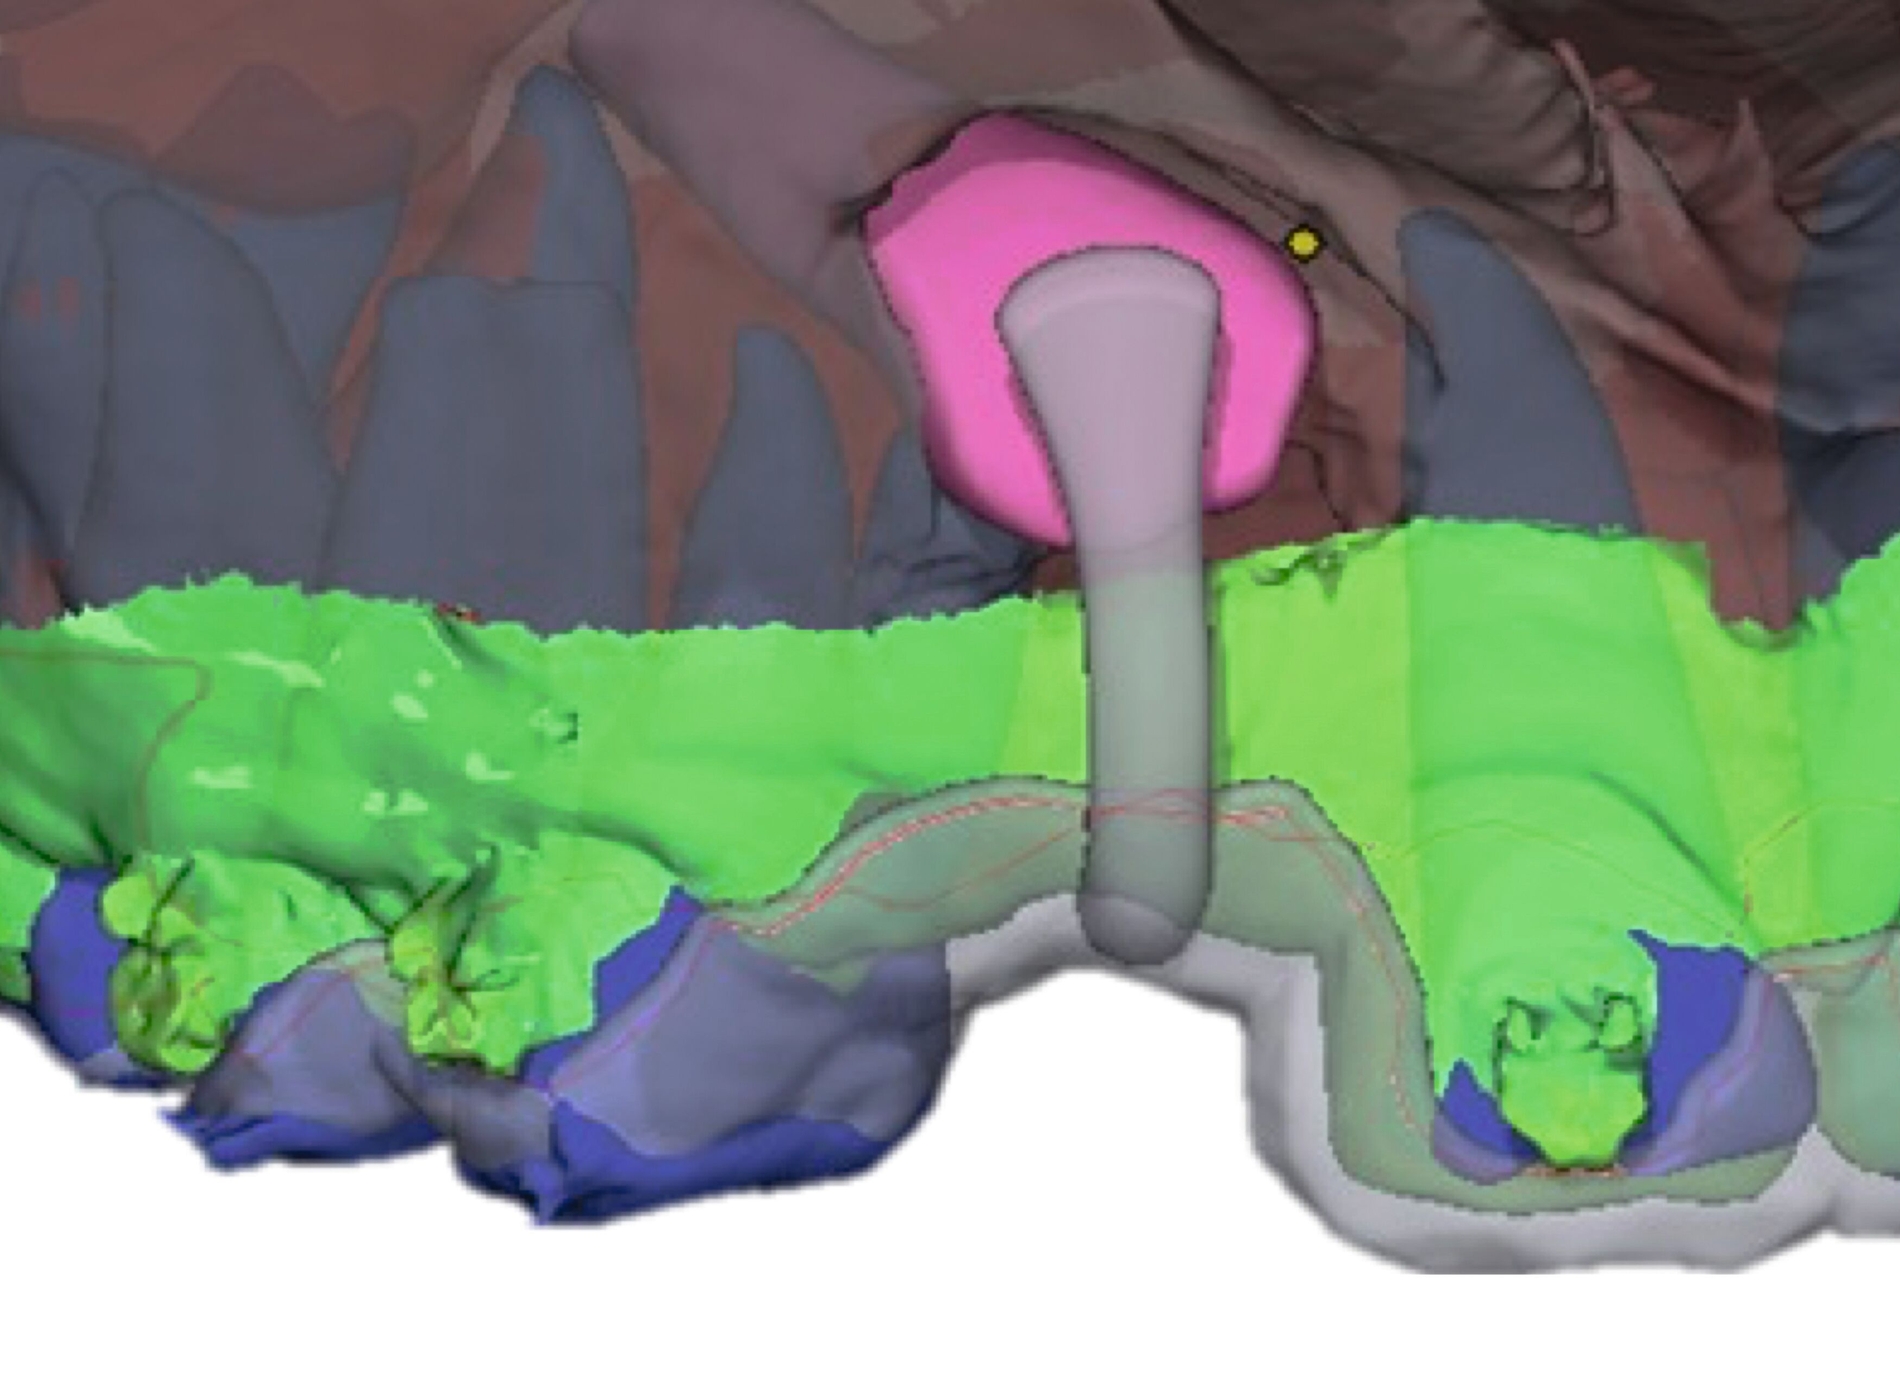

In Absprache mit dem/der zahnärztlich beziehungsweise chirurgisch tätigen Kollegen/in kann die Kieferorthopädie durch Umsetzung verschiedenster 3-D-gedruckter Elemente eine Hilfe in interdisziplinären Behandlungen bieten. Am Beispiel der Zahntransplantation ermöglicht der 3-D-Druck zuvor im DVT segmentierter Zähne eine passgenaue Vorbereitung des Transplantationsbettes (Abbildung 6a). 3-D-gedruckte Zähne können darüber hinaus als Lückenhalter während der kieferorthopädischen Behandlung dienen (Abbildung 6b), bevor eine definitive Versorgung durch den/die zahnärztliche/n Kollegen/in erfolgt.

Weitere Beispiele beinhalten hochkomplexe Behandlungsfälle multipler Zahnanlagen. Während die Extraktionsentscheidung und Absprache mit dem/der chirurgisch tätigen Kollegen/in allein auf Basis der Bildgebung oft limitiert ist, erleichtern 3-D-gedruckte Modelle des segmentierten DVTs sowohl die Entscheidung als auch die Absprache und ermöglichen darüber hinaus eine genauere Planung des chirurgischen Vorgehens (Abbildung 6c). Gleiches betrifft parodontalchirurgische Eingriffe, in denen sogenannte „Cutting guides“ eine zuvor digital geplante Gingivektomie ermöglichen (Abbildung 6d). Im Bereich der Freilegung verlagerter Zähne können Schablonen dem/die chirurgisch tätigen Kollegen/in sowohl die Freilegung des Zahnes (Abbildung 6e) als auch die Anbringung eines Attachments (Abbildung 6f) erleichtern und dabei die kieferorthopädisch gewünschte Attachmentposition passgenau übertragen.